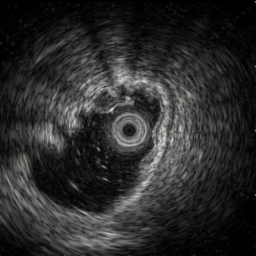

SMTs: We collected a private dataset consisting of image-report pairs related to submucosal tumors (SMTs) of the gastrointestinal tract from the Third People’s Hospital of Chengdu. The study was conducted in accordance with the Declaration of Helsinki and was approved by the Ethics Committee of the Third People’s Hospital of Chengdu on September 25, 2024 (IRB No. 2023-S-48-1). Due to the retrospective nature of the study, the requirement for informed consent was waived. To ensure patient privacy, all personally identifiable information has been removed. The dataset includes EUS (Endoscopic Ultrasound) images and corresponding textual reports collected from five different hospitals. We used data from four hospitals to construct our pretraining dataset, comprising 2455 (547), 266 (68), and 600 (120) EUS image-report pairs for the training, validation, and test sets, respectively. The numbers in parentheses indicate the quantities grouped by patient ID. Data from the same patient were assigned exclusively to a single split to ensure fair and non-overlapping partitioning. The data from the remaining hospital were reserved for downstream task evaluation.

SMTs 3×200: We use the SMTs pretraining test set as a downstream task subset, which includes three tumor categories (gastrointestinal stromal tumors (GISTs), neuroendocrine tumors (NETs) and Leiomyomas) randomly sampled from four hospitals, with 200 image-text pairs per category. Each instance in the dataset belongs to a single tumor category.

SMTs SN: This dataset is an image-text dataset with the same structure as the SMTs dataset, obtained from a single hospital. It contains 584 pairs of data from 120 patients, covering four categories: GISTs, NETs, leiomyomas, and others. Each example belongs to a single abnormality category.

5.2 Visualization of attention weights

Fig. 5 presents a qualitative visualization of the learned word-to-region correspondences facilitated by our AGA framework. The top row shows the original medical images, including both chest X-rays (CXR) and endoscopic ultrasound (EUS) images. The bottom row displays the corresponding heatmaps generated by our model, where warmer colors denote higher activation weights, indicating stronger associations between specific image regions and the given medical concepts. For Atelectasis and Pneumonia, the model focuses on appropriate pulmonary regions, demonstrating strong localization aligned with radiological pathology. For the SMTs domain, terms like low-echoic mass and protruded into the cavity activate precisely the relevant interior structures of the lesion in EUS images. The distinct and interpretable activation patterns validate the effectiveness of our AGA mechanism in achieving fine-grained multimodal alignment.

low-echoic

mass

protruded

into the

cavity

clear

boundaries